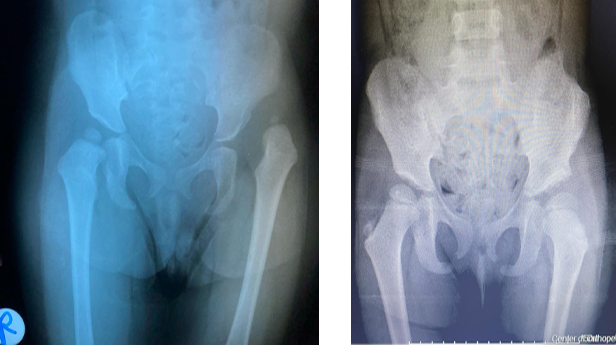

Hip dysplasia in children and adolescents

If a baby is born in a breech position, a pediatrician can detect or diagnose hip dysplasia with ultrasound. Our team treats children with this disorder by non-surgical means, in addition to surgical procedures if necessary.